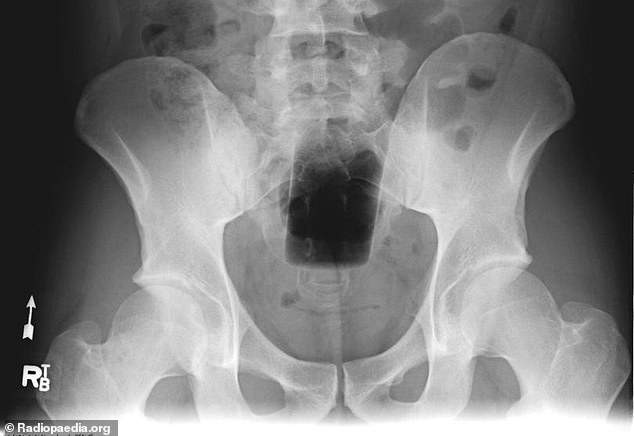

X光机下拍到的各种异物

妹妹・牙刷・金属塑料容器・胶带・被逮捕时急忙塞进去的手机・香水罐・化妆棉・内衣・玩具扭蛋・橡胶球・汤匙